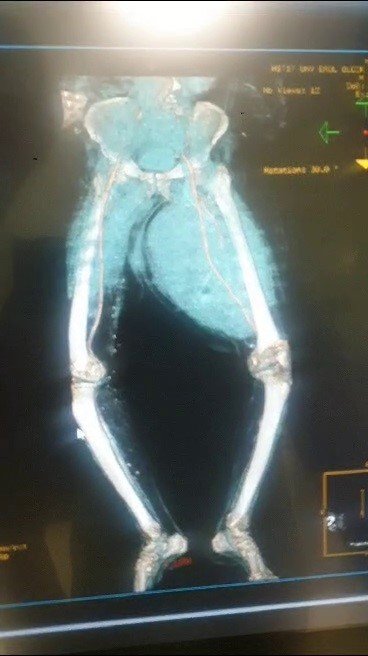

Çorum'da, ayaklarındaki ağrı ve şişlik sebebiyle 4 aydır sağlık sorunları yaşayan Haydar Yatar, Hitit Üniversitesi Erol Olçok Eğitim ve Araştırma Hastanesi'ne başvurdu. Burada yapılan muayenede Yatar'ın ayaklarındaki şişliğin sebebinin tümoral bir kitle olduğu belirlendi. Tıp Fakültesi Ortopedi ve Travmatoloji Anabilim Dalı Başkanı Doç. Dr. Murat Çalbıyık ve ekibi tarafından yapılan 4 saatlik başarılı bir operasyonda Yatar'ın uyluk kemiğinden 8,9 kilo tümör çıkartıldı. Başarılı ameliyat sayesinde 4 aydır çektiği acılardan kurtulan Haydar Yatar, sağlığına kavuştu.

Ortopedi ve Travmatoloji Anabilim Dalı Başkanı Doç. Dr. Murat Çalbıyık da hastanın yaklaşık 4 aydır sağ ve sol uyluk kemiğindeki şişlik şikayetiyle kendilerine başvurduğunu belirterek, "Hasta daha önce bir bypass ameliyatı kalp ameliyatı olduğundan dolayı hastalığın uyluk kemiğindeki şişliğin burada kanamaya bağlı olduğu düşünülmüş. Bize sevk edildiğinde yaptığımız tetkiklerde uyluk bölgesinde 8 kilo 900 gram bir tümör olduğunu tespit ettik. Bu büyük bir tümördü. Tüm damar çevresindeki tümörü çıkararak hastamızı sağılığına kavuşturduk. Hastamızın tüm takiplerini yapıyoruz" diye konuştu.